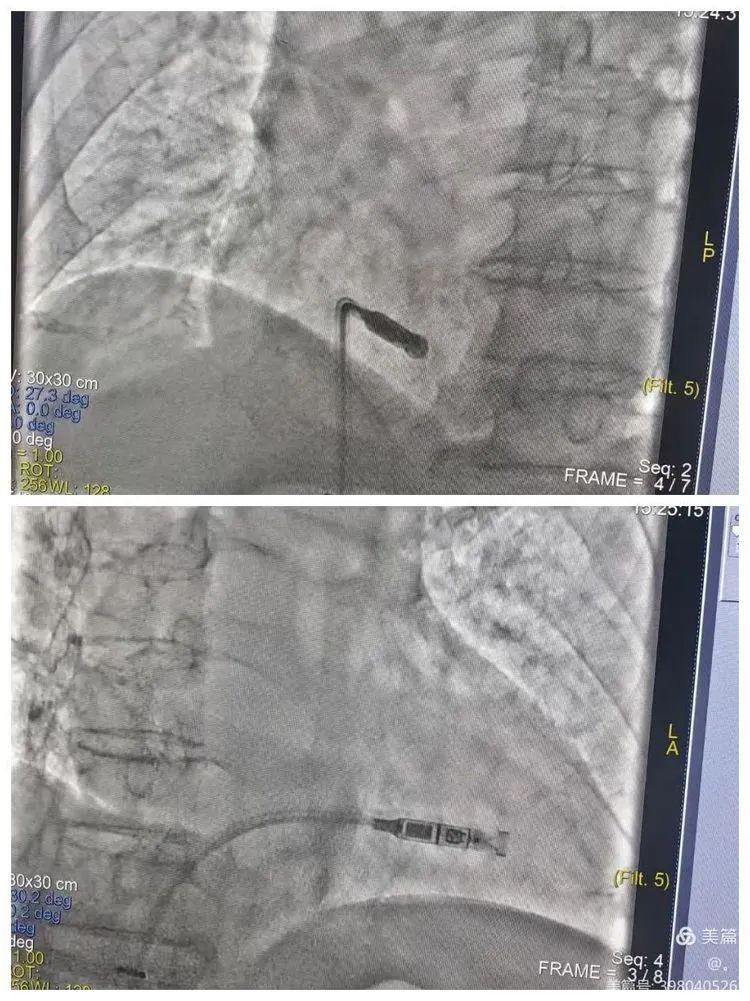

2024年5月6日心血管內(nèi)科心衰病區(qū)在劉志遠(yuǎn)主任團(tuán)隊(duì)的共同努力下,為一位八十八歲高齡的患者成功置入了Micra VR(無導(dǎo)線起搏器),為老人帶來了“心”的健康,同時(shí)也改善了病人的生活質(zhì)量。

無導(dǎo)線起搏器是集脈沖發(fā)生器與電極導(dǎo)線于一體的新型起搏器,無需靜脈植入心內(nèi)膜導(dǎo)線,而是以微縮膠囊的形式植入患者的心腔內(nèi),因此也無需皮下切口和囊袋。被媒體譽(yù)為“全球體積最小的心臟起搏器”。